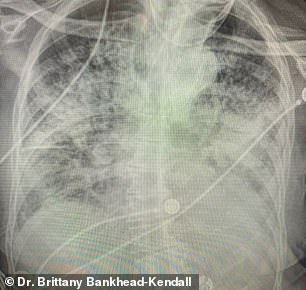

박사는 공개한 건강한 사람, 골초 흡연자 그리고 코로나19 환자의 폐 사진 3장을 보면 건강한 사람의 사진은 폐에 검은색 공간이 많은 모습을 보여준다. 즉 산소를 받아들일 수 있는 면적이 많은 건강한 폐이다. 반면 흡연자의 사진에서는 폐 내부의 염증과 손상을 나타내는 하얀색 실선이 많은 모습이 관찰된다.

하지만 코로나19 환자의 사진 속 폐는 대부분 흰색으로 변해 있다. 이는 폐 속에 남아 있는 온전한 세포가 많지 않아 환자가 폐로 충분한 산소를 받아들일 수 없다는 것을 의미한다.